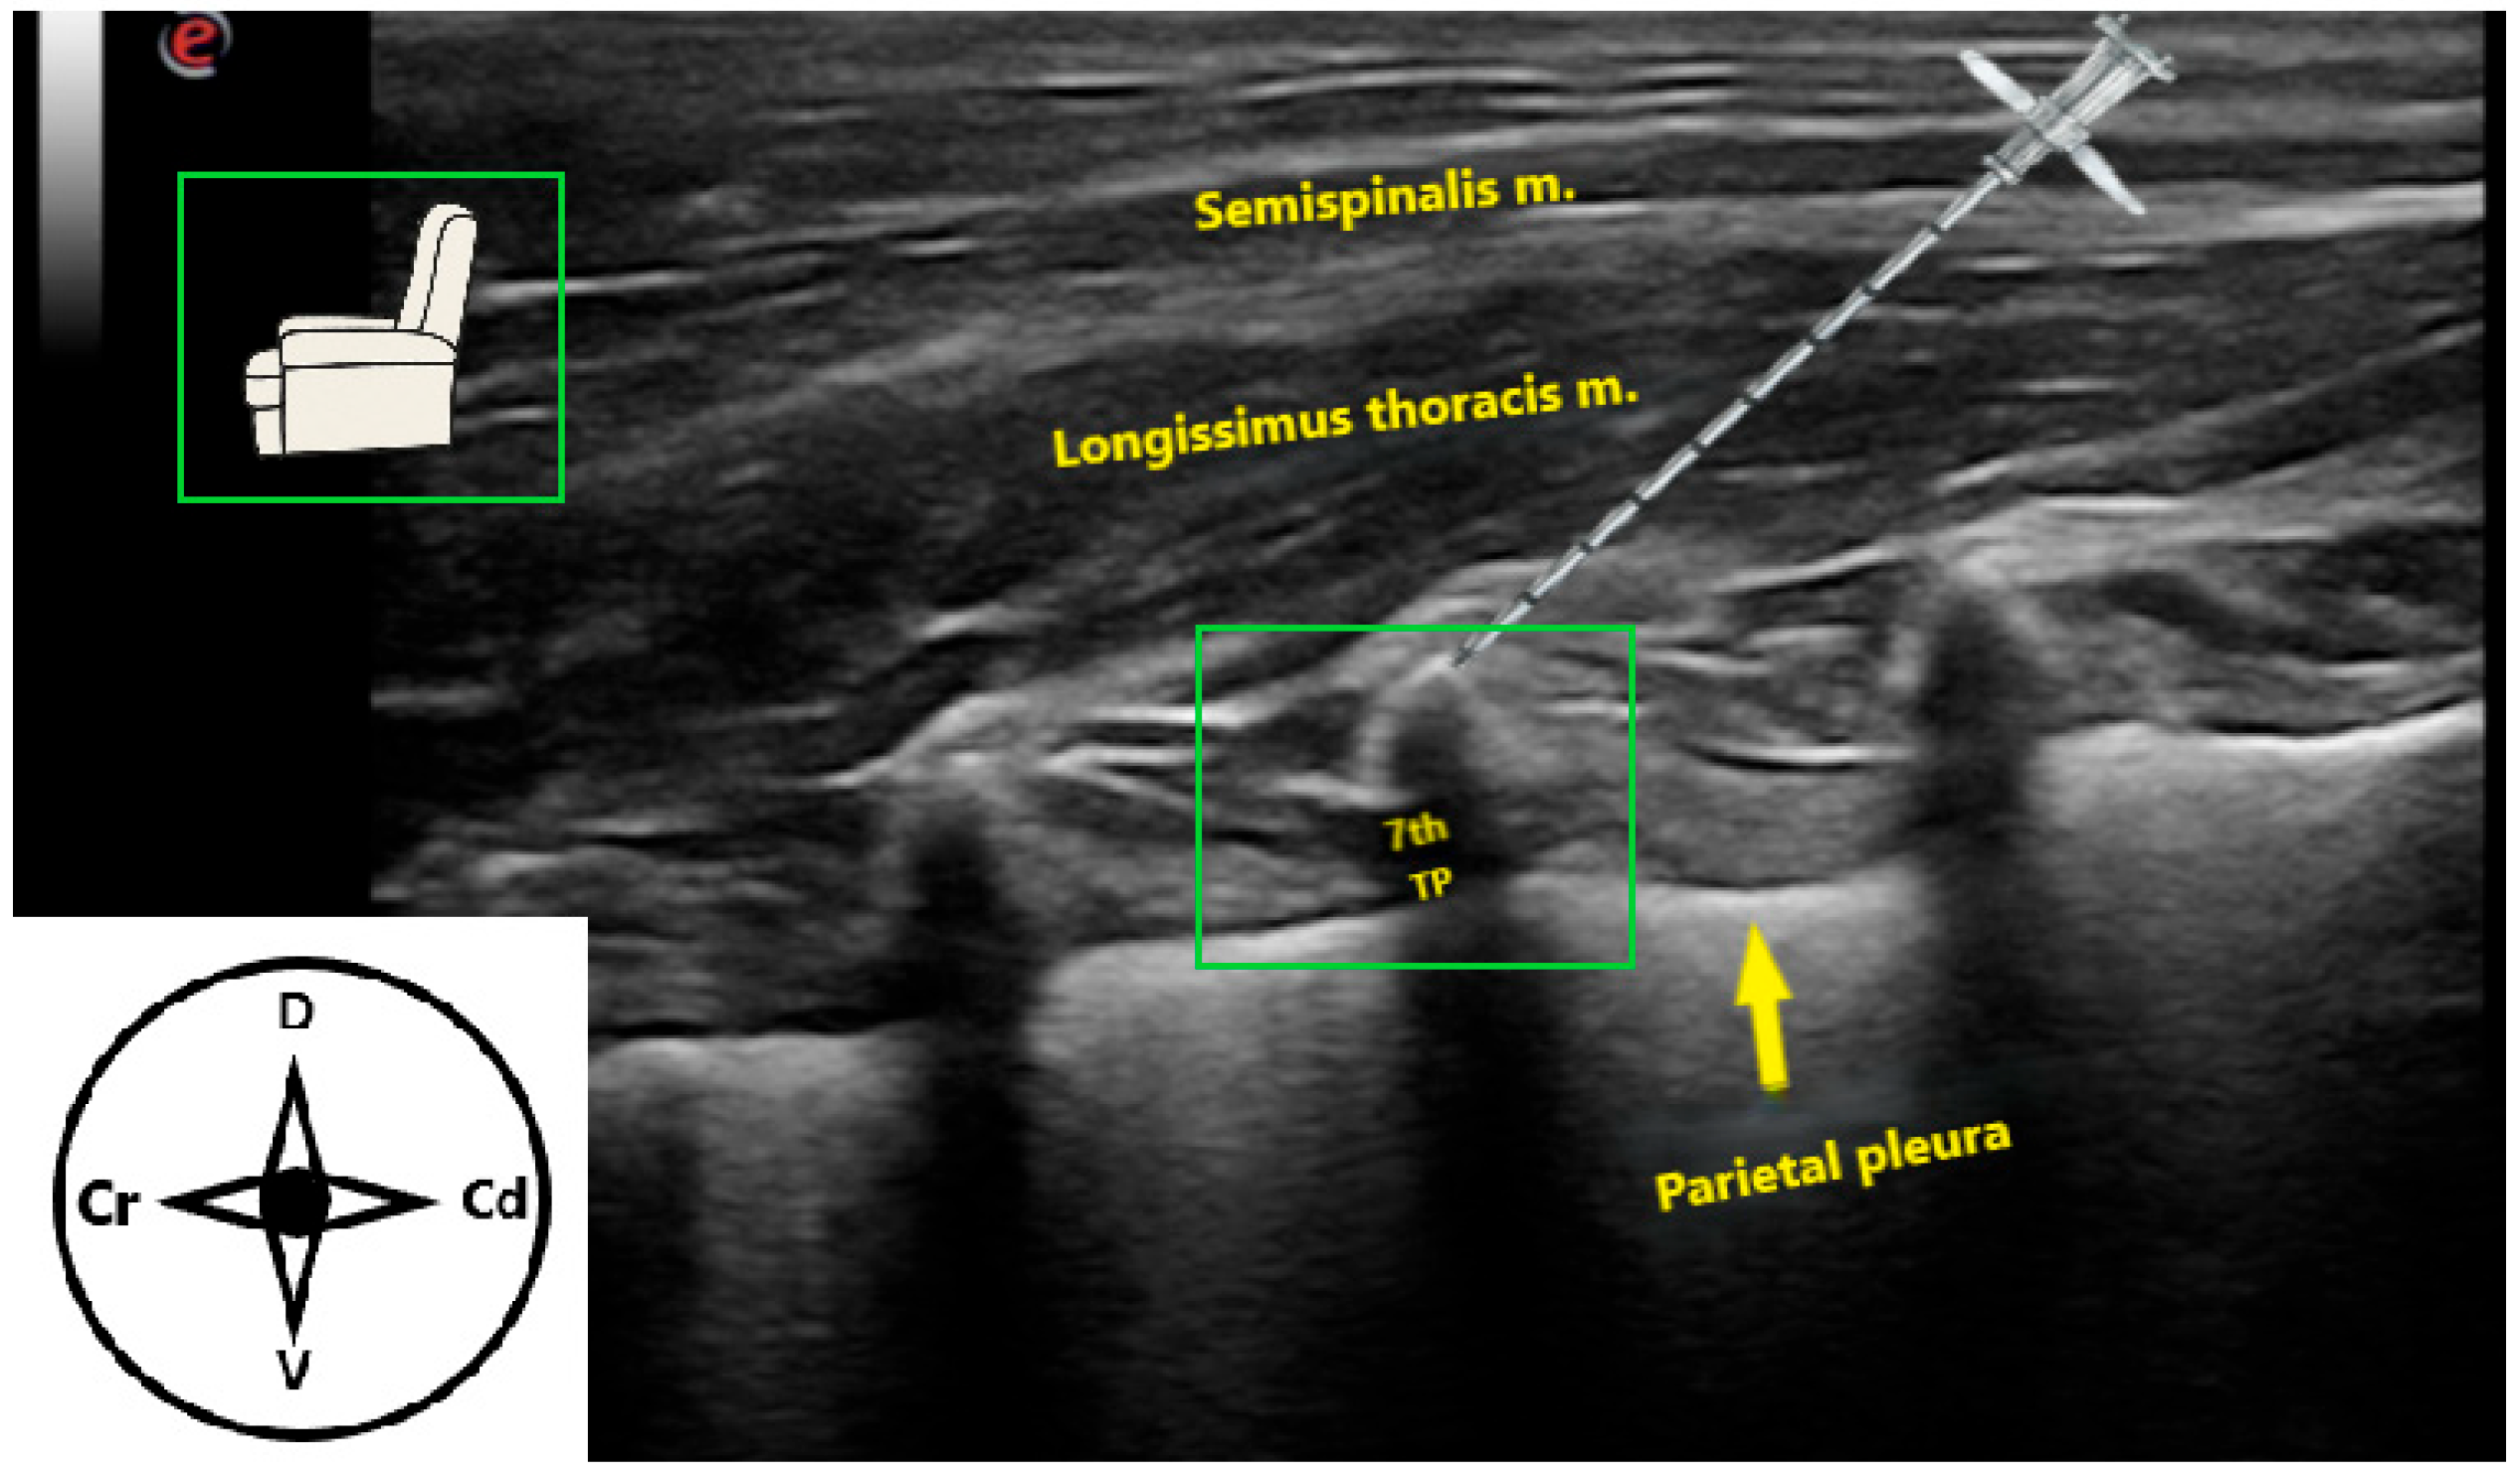

3.2. Ultrasound-Guided Technique